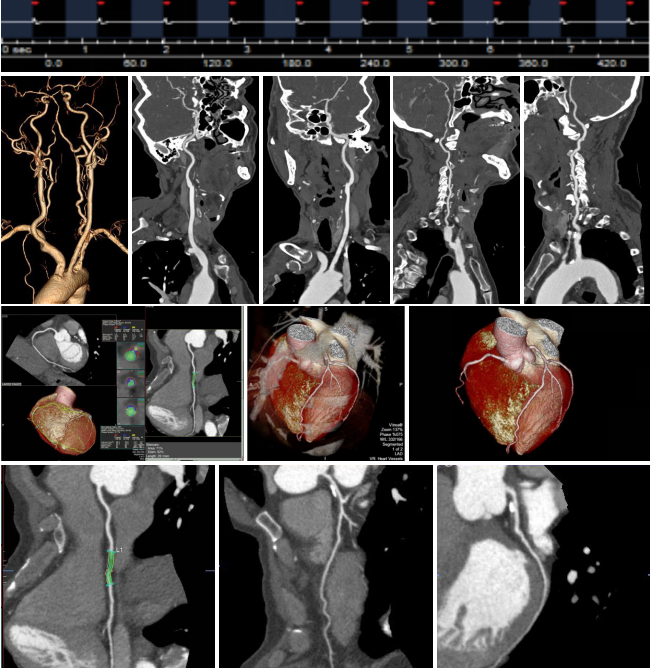

病例四 男,64歲, 頭暈胸悶查因。 執(zhí)行頭頸血管+心臟冠脈一站式低劑量掃描。

一次掃描 、一次打藥60ml完成頭頸心一站式掃描,各血管及小分支清晰可見(jiàn) , 頸 部 血管未見(jiàn)明顯異常, 冠脈有狹窄及多發(fā)斑塊。

病例三 女,51歲, 近一年經(jīng)常性不明原因胸痛

一次掃描、一次打藥70ml,冠脈+全腹CTA掃描,可見(jiàn)冠脈血管多發(fā)斑塊,腹部血管CTA未見(jiàn)異常。

該檢查使用640層寬體探測(cè)器CT160排螺旋掃描技術(shù),實(shí)現(xiàn)了全身大范圍CTA檢查以及胸痛三聯(lián)征一站式檢查,僅需一次藥,在一次掃描中實(shí)現(xiàn)采集。

病例四 PCI后復(fù)查,前降支支架內(nèi)再狹窄。

冠脈減影前 冠脈減影后

病例五 高鈣化積分冠脈檢查